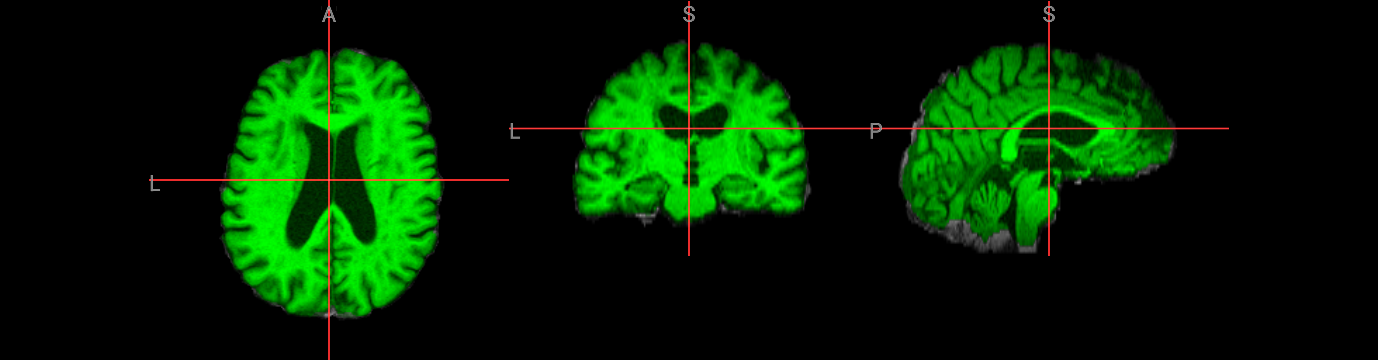

Varying the fractional intensity threshold parameter (-f)#

The fractional intensity threshold is BET’s key parameter for distinguishing brain tissue from non-brain tissue. This interactive demonstration shows how different -f values affect brain extraction results:

Lower values (e.g., -f 0.2): More inclusive extraction - captures more tissue but may include non-brain areas

Higher values (e.g., -f 0.8): More conservative extraction - tighter brain boundary but may exclude brain tissue

Default (-f 0.5): Balanced approach suitable for most cases

The folowing visualization shows three different threshold results overlaid on the original image, demonstrating how this single parameter dramatically changes the extraction outcome.

nv.load_volumes( [{"path": "./output/structural_brain_f02.nii.gz", "colormap": "gray"},

{"path": "./output/structural_brain.nii.gz", "colormap": "green"},

{"path": "./output/structural_brain_f08.nii.gz", "colormap": "red"}])